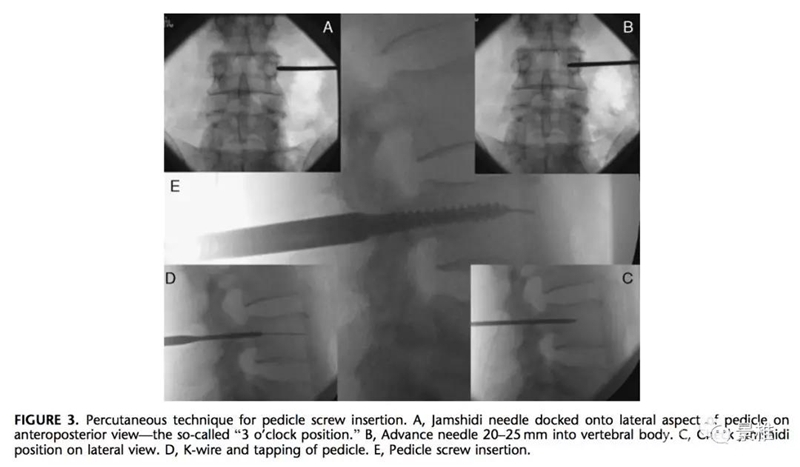

进针点确认(A&B)

因为椎弓根穿刺路径倾斜,所以椎弓根投影到皮肤上的进针点是椎体正位透视下的横突尖部。肥胖者和正常人距离略有些不同。

经椎弓根的标准穿刺通道有三个重要的透视定位点:上关节突外下缘①,椎弓根中点②,椎体后缘与椎弓根内侧缘交点附近③。

穿刺路径确认(C&D)

穿刺过程中,每一次深入,均需正、侧位透视,每个定位点都一一对应。

1.正位片上确认横突尖部在体表的投影,从此处进针,斜向椎弓根眼的3、9点位进入。

2.刚进入时,针尖正位在①椎弓根外缘,侧位在①椎弓根后缘。

3.再进20-25mm,针尖正位显示进入到③椎弓根内缘,侧位应到③椎体后缘。

4.上述正侧位透视若不一致,意味着穿刺角度不对,需及时调整,以防进入椎管。